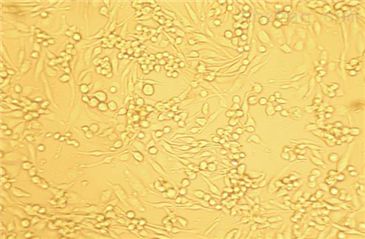

- 生长状态:

贴壁生长

HIC(人小肠癌细胞)复苏